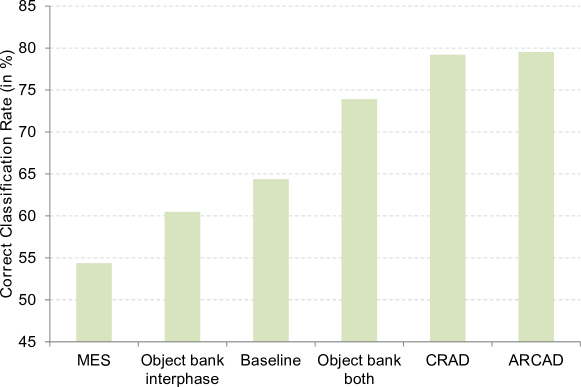

In the second evaluation we contrasted the proposed approaches to existing methods for HEp-2 specimen image classification. The most common approach for classifying specimen images is to use the dominant pattern of the interphase cells [7, 22, 5, 24]. Here, we call this baseline. Another approach, here denoted Multiple Expert System (MES), is to train individual classifier for each class (i.e. one interphase cell classifier for each class) and use the classification reliability score to do weighted voting [17]. We implemented both baseline and the MES approach.

We also implemented the approach in [12] which proposes the concept of Object Bank. Technically, we train k one-versus-all classifiers. Given a cell image, we apply all the k classifiers and consider the k classification output scores as the object bank representation of the cell. The object bank representation of a specimen image is obtained by averaging the cell-level object bank representation. Here, we trained two sets of classifiers: (1) eight classifiers trained on interphase cells (i.e. one classifier for each pattern class), denoted Object bank interphase; (2) sixteen classifiers consisting of eight classifiers trained on the interphase cells and eight on the mitotic cells, denoted Object bank both.

Fig. 4 presents the evaluation results. The proposed approaches significantly outperform all other methods. We note that the MES has poor performance which contradicts what was reported in [17]. Upon a closer look we found that some classes such as Mitotic Spindle do not have specific characteristics on their interphase cells. Henceforth, it is difficult to train a reliable cell classifier rendering much lower reliability score. In other hand, traditional voting (i.e. the baseline) has much better performance as it only counts the vote and does not consider the classification reliability score. Furthermore, we found that combining the information extracted from both interphase and mitotic cells is of importance. This can be observed from the fact that there is a significant increase in Object bank performance when information from both cell types is used.